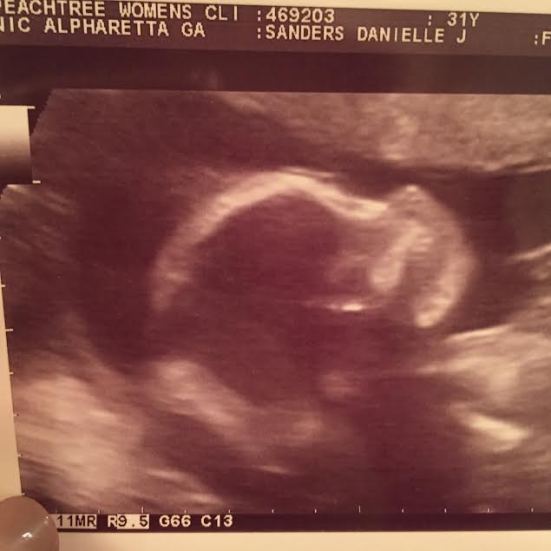

Baby girl looked great on the ultrasound, too! Strong heart, brain looks good and everything appears to be where it’s suppose to be. Heartbeat is still 156!